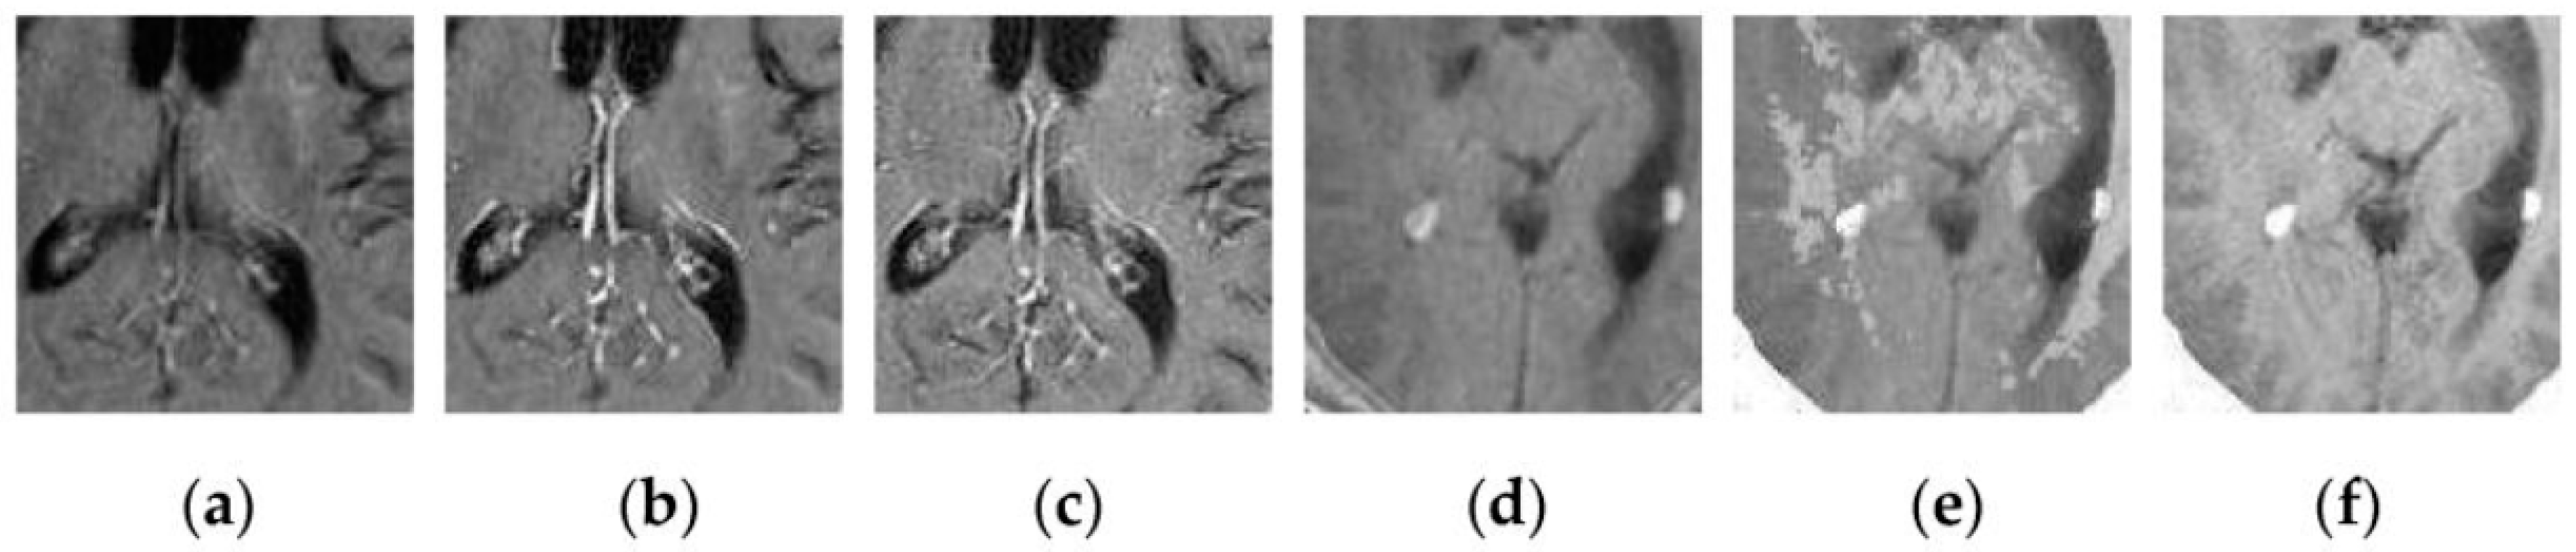

To further verify the advantage of the proposed SCM-M method in multimodal image fusion, Figure 11 and Figure 12 show the enlarged views of fused results for all evaluated methods operating on regions of interest (ROIs) denoted by the red boxes in Groups 1 and 6 in Figure 6, respectively. Figure 13 shows the enlarged views of fused results for the proposed method, the m-PCNN method and the SCM-F method operating on ROIs denoted by the red boxes in Groups 7 and 8 shown in Figure 6. In Figure 11 and Figure 12, we can see that the SCM-M method can maintain the salient information in the source images and provide better visual perception with less loss in luminance or contrast than other compared methods. To explain this point better, some edges and regions have been chosen from Figure 11g and Figure 12g. It can be seen from Figure 11 that the SCM-M method can provide better edge preservation than all other methods as pointed by the three red arrows. Meanwhile, compared with the DWT, NSCT and NSCT-SR methods, the SCM-M method can maintain the information in the MR image shown in Figure 6f better without introducing artifacts as indicated by the two red boxes. In Figure 12, we can see that the proposed method can keep the integrity of the edge marked by the red arrow best among all evaluated methods. Likewise, as pointed by the green arrow, the edge can be preserved very well by the proposed method while it has been damaged very seriously by other methods. Besides, the sharpness of the region shown by the red box can be maintained by the proposed method better than by the compared method. Furthermore, it can be seen in Figure 13 that compared with the m-PCNN and SCM-F methods, the SCM-M method can preserve fine image details and maintain image contrast better.

Figure 13.

Enlarged views of fused results of ROIs denoted by the red boxes in Groups 7 and 8 shown in Figure 6 for the m-PCNN, SCM-F and SCM-M methods: (a) the m-PCNN method for Group 7; (b) the SCM-F method for Group 7; (c) the SCM-M method for Group 7; (d) the m-PCNN method for Group 8; (e) the SCM-F method for Group 8; and (f) the SCM-M method for Group 8.